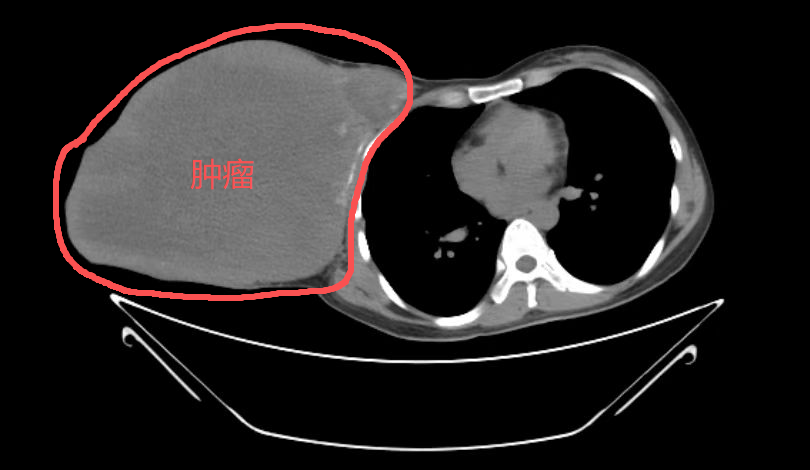

反复血尿2个月,49岁男子查出"百万分之一"罕见癌!

49岁的王先生(化名)从未想过,自己反复出现的无痛性血尿,会牵出一个“隐匿杀手”,并最终指向一个连泌尿外科医生都极少遇见的恶性肿瘤——脐尿管癌。

十年拖延,女子胸前赘生5公斤重肿瘤!医生术后郑重告诫…...

2026-01-22